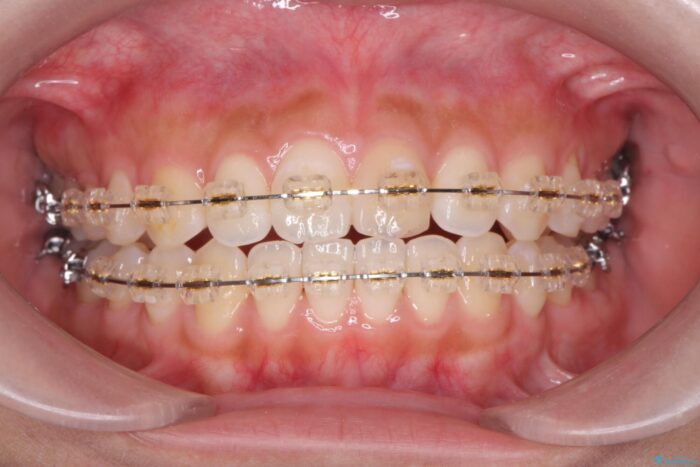

仕上がりにこだわりたいと、装置はマウスピースではなくワイヤーを希望されました。

マルチブラケットを用いた非抜歯のワイヤー矯正で噛み合わせと歯並びを改善していきます。

1年で歯並び、嚙み合わせともにしっかりと改善されました。

患者様にも、非常に噛みやすくなったと喜んでいただくことができました。